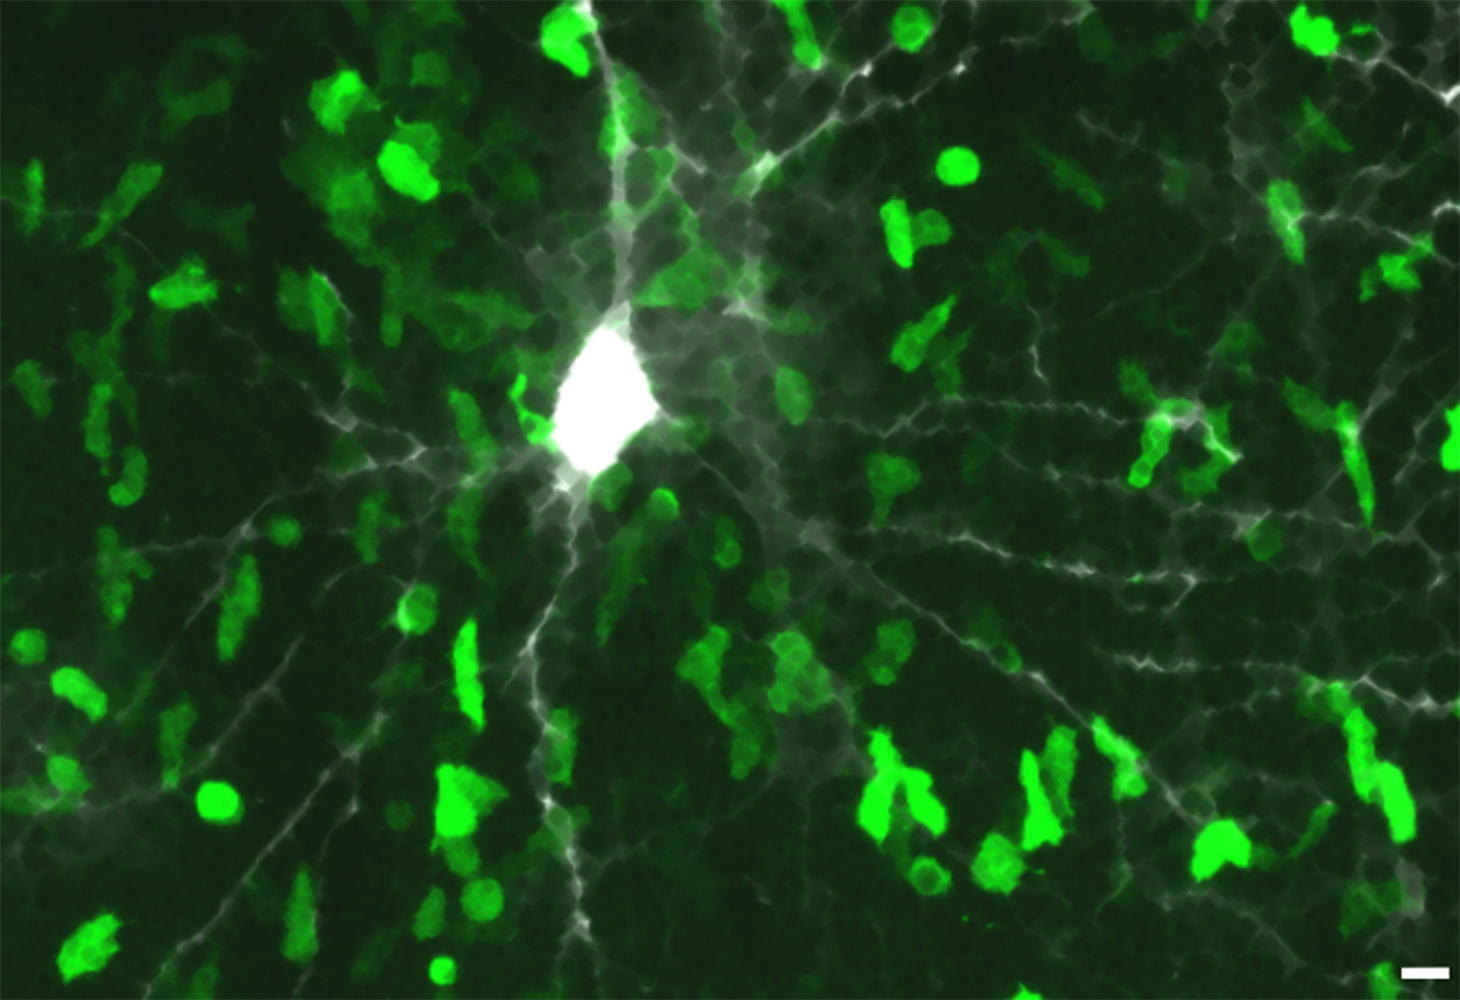

IMAGE: T cells targeting beta-synuclein invade the grey matter. Shown here is a rat’s brain cortex, one frame of a microscopic recording. The pathogenic T cells (green) have infiltrated the grey matter tissue in great numbers. One can see some of these T cells in direct contact with a nerve cell and its axons (grey-white). Magnification bar: 10µm. Image: Institute for Neuroimmunology and Multiple Sclerosis Research.

Immune cells targeting the protein beta-synuclein present in neurons invade the brain’s control center and trigger an inflammatory reaction there. This inflammation damages the grey matter’s highly specialized and fragile neural network. The disastrous result: the brain shrinks and there is an irreversible neurological loss of function. The Goettingen researchers also discovered that such destructive immune cells are particularly numerous in the blood of patients with multiple sclerosis of the chronic-progressive course. This finding could be relevant for diagnostic and therapeutic aspects of multiple sclerosis.

“Unexpectedly, the animals’ brains showed completely dissimilar disease signs. Also the lesions were different in that the pathological cells nearly exclusively invaded the grey matter”, says Dr. Francesca Odoardi, co-senior author of the study. This inflammation caused – above all after several flare-ups – an irreversible damage and shrinkage of the grey matter, similar to what is observed in humans with multiple sclerosis. Indeed, the researchers found that beta-synuclein-targeting T cells were present in higher numbers in the blood of multiple sclerosis patients, and an especially high number in those with a chronic-progressive disease course.